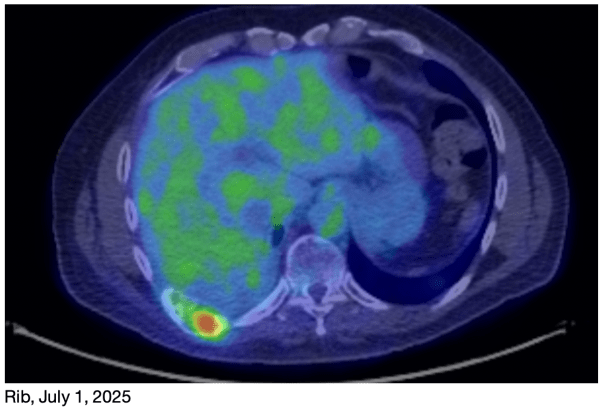

This is a brief but important cancer update. I know it’s been a long time since my last update, but we haven’t had significant news for awhile. As you’ve read before, I’m going through a new set of chemo treatments right now, in response to my July PET scan results. I’m in my 4th round right now, with my 5th of 6 scheduled treatments happening next week. My NGS test results from a few weeks ago show that the new rib tumor is genetically the same as the original one, so the same chemo agents should continue to be effective.

I had another PET scan on Tuesday of this week. The results are very encouraging!